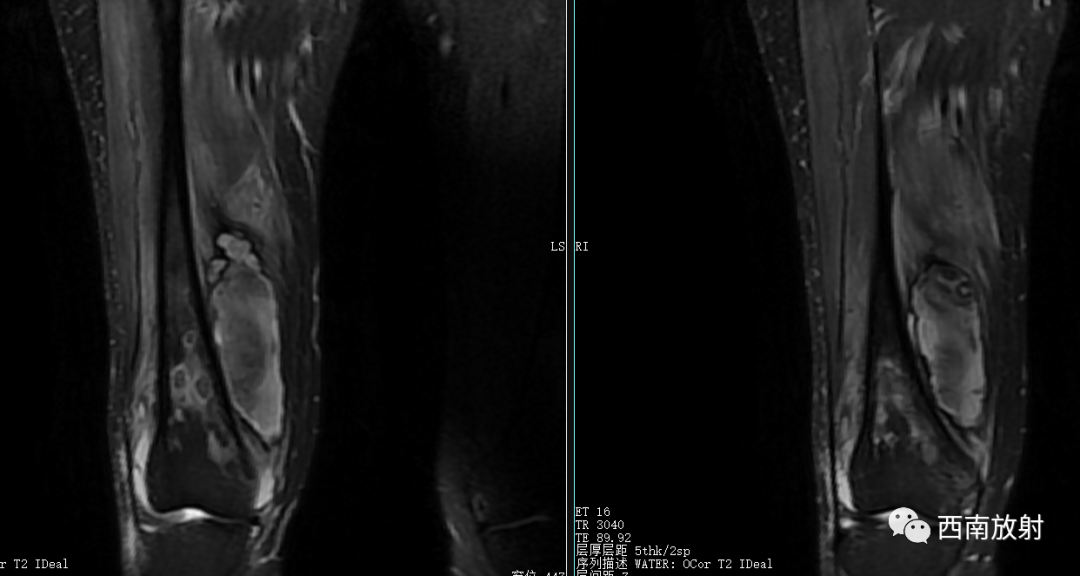

现病史:患者于2021年8月17日开始出现右膝关节疼痛,无畏寒发热、恶心呕吐、咳嗽咳痰,无破溃、流脓,于8月20日在我院急诊科就诊,考虑关节炎,予口服双氯芬酸钠缓释片及泼尼松等药物治疗,无好转,随后转到天等县中医院就诊,予行右膝关节抽液及外敷中成药治疗(具体不详),4天前开始出现解黑便,每日1次,每次量约200g,伴有头晕、乏力,无腹痛、呕血、昏迷及呼吸困难等。今来院就诊,在门诊发现血压偏低,85/56mmHg,右膝关节抽出45ml的红色积液,右膝关节MRI示有骨髓炎,生命征不稳定,有转入我科指征,我科会诊后转入治疗。患者病后精神、睡眠差,未进食,大便如上述,小便色黄,量尚可,体重无明显变化。

大体病理:右大腿中下段内侧骨膜外见一腔隙,约3X3X4cm,内有较多血凝块,有少许脓液,股骨下段周围有少许脓液,少量疤痕形成,右膝关节内有少许脓液,见有少许脓苔,右骨髓腔未见破坏,骨髓腔内有少许脓液,已被疤痕织包裹。

诊断:慢性骨髓炎,周围软组织脓肿。

CT显示骨破坏、脓肿、死骨及骨膜增生、骨质增生硬化,呈骨小梁密度增高、模糊,髓腔密度增大、狭窄,皮质增厚。MRI显示早期骨髓内广泛分布的斑片异常信号,与邻近正常骨髓信号相比较,T1WI信号减低,T2WI信号增高,脂肪抑制T2WI 或STIR 等序列上病变显示更清楚,骨皮质周围软组织内呈弥漫分布的T1WI低信号及T2WI高信号影,边界模糊。出现骨膜反应,骨皮质不规则破坏,脓肿及死骨形成。